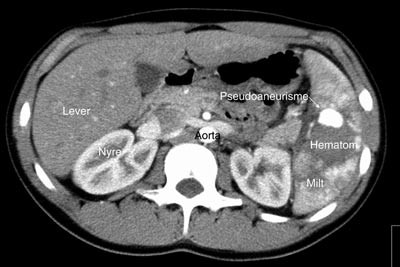

Pasient 2. En 20 år gammel mann ble utsatt for en trafikkulykke. Han var komatøs og ble intubert på skadestedet. CT-undersøkelse ved Ullevål universitetssykehus viste venstresidig pneumothorax og costafrakturer. I milten forelå en laserasjon kaudalt (skadegrad III), men normale funn i hilusnivå (e-fig 4). Pasienten ble observert og overflyttet til lokalsykehus etter tre dager. Seks dager etter traumet ble det gjort en CT-kontroll med arteriell kontrastfase. Denne viste en tilkommet, høytattenuerende lesjon ved milthilus, forenlig med et pseudoaneurisme (e-fig 5). Pasienten ble flyttet tilbake til Ullevål universitetssykehus hvor det ble utført angiografi med embolisering (e-fig 6). Ultralydkontroll samme dag viste opphørt sirkulasjon i lesjonen. Tre dager senere ble pasienten utskrevet.